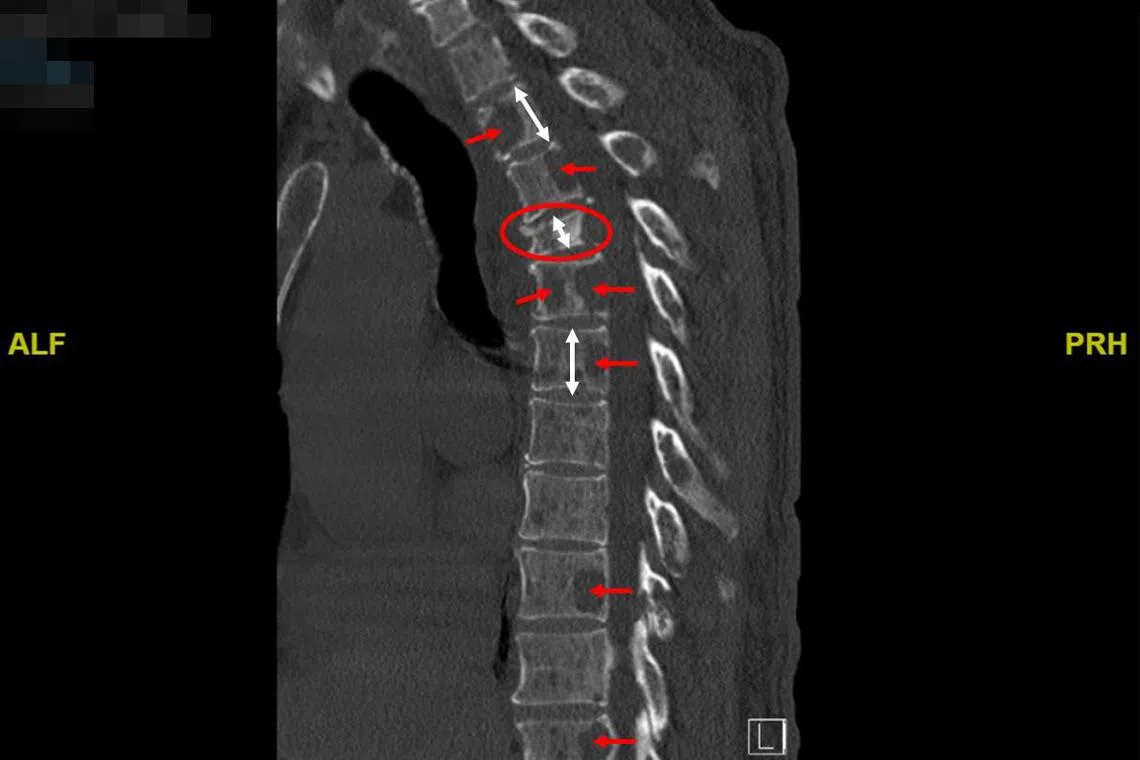

癌症也对王明星的骨骼系统造成破坏性影响,他的脊柱出现多处空洞,为此通过手术植入一根有12颗螺钉的金属棒以支撑。但是,这并不能阻止癌细胞侵蚀他的骨骼系统,植入材料也可能成为细菌播种的病灶。